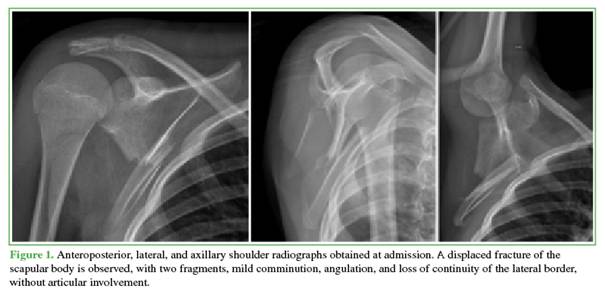

Radiographs (Figure 1) revealed a displaced fracture of the right scapular body with two fragments.

A computed tomography scan with three-dimensional reconstruction (Figure 2) showed a markedly compromised glenopolar angle measuring 20.88°. Comminution of the scapular body was also identified, along with displacement of the lateral wall with a 45° inclination and medialization.